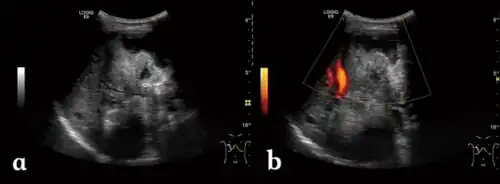

| a) Irregular type heterogeneous mass lesion b)no obvious blood flow signal | |